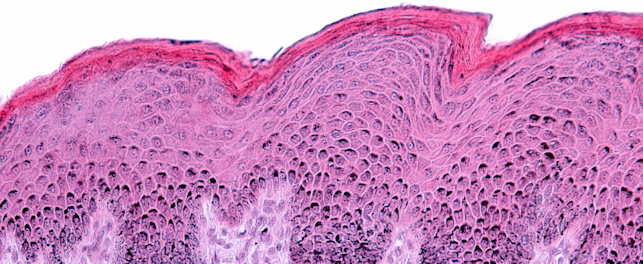

• Microbiological analyses: hygiene control, conservation tests